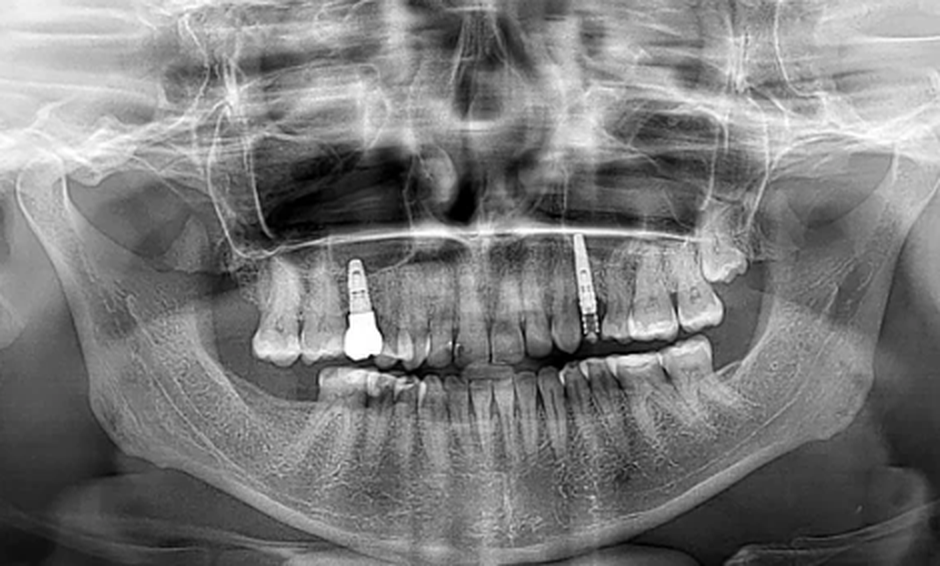

Das Bild zeigt eine sogenannte Panoramaschichtaufnahme (OPG) des Kiefers. Diese spezielle Röntgentechnik ermöglicht eine umfassende Darstellung von Ober- und Unterkiefer, den vorhandenen Zähnen, dem Kieferknochen sowie bereits gesetzten Implantaten. Im dargestellten Fall sind im Oberkiefer Implantate sichtbar, die als künstliche Zahnwurzeln dienen und die Grundlage für festen Zahnersatz bilden. Bei MKG Köln West nutzen wir solche Aufnahmen, um Behandlungen präzise und sicher zu planen.

Jede erfolgreiche Implantatversorgung beginnt mit einer exakten Analyse. Nur wenn die Ausgangssituation genau verstanden wird, lässt sich die Behandlung sicher und langfristig stabil umsetzen. Dieses Röntgenbild steht exemplarisch für unseren Anspruch bei MKG Köln West: höchste Präzision, maximale Sicherheit und individuelle Lösungen.